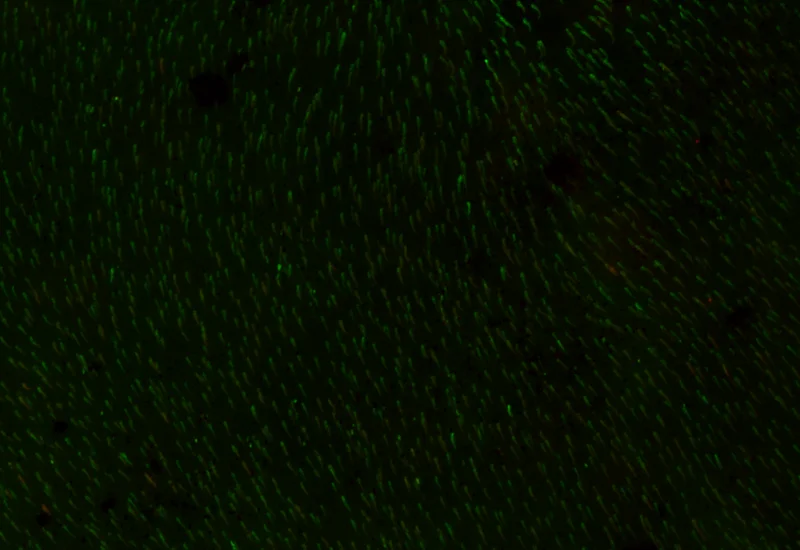

Original Image

Rods and Cones detection

IF Rods & Cones in Retina

Detect rods and cones based on specific staining, quantify structure number, length, and density, and measure number, percentage, and density of marker-positive rods and cones.

The IF Rods & Cones in Retina App detects the rods and cones based on specific staining. It outputs the number, density and length of detected structures as well as the number, percentage and density of marker-stained rods and cones.